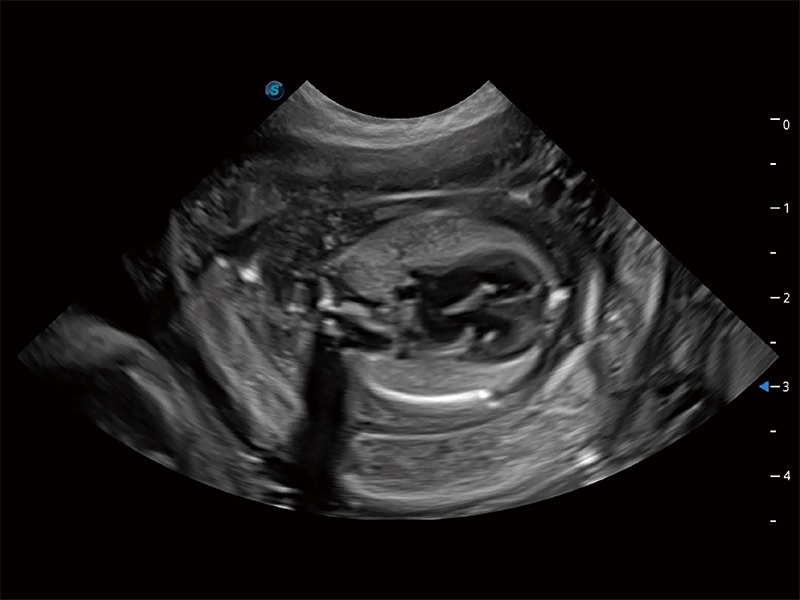

动物是人类最亲密的朋友和最值得信赖的伙伴。milan米兰也一直致力于探索动物专用的超声影像解决方案。全新推出的ProPet系列,是milan米兰在动物超声影像智能化、专业化、精准化的一次跨越式革新。动物不能用言语来表述自己的不适,通过超声影像,ProPet系列搭建了动物医生与不同物种沟通的“桥梁”,为动物医生注入了“治愈之力”。 ProPet 80 是milan米兰匠心打造的一款高端动物专用彩超,采用性能卓越的全新硬件架构,极大提升超声系统的运行效率和数据处理能力,帮助动物医生从容应对日益增多的挑战性病例和日益多样化的临床需求。

高性能和先进的临床应用工具可以为动物医生提供临床信心。ProPet 80 搭载了先进的腹部和浅表应用工具,帮助医生在日常临床实践中发挥前所未有的作用。

ProPet 80 专为动物医生设计,对不同的动物体型和生理结构作出了针对性的优化。通过动物影像专用软件,可满足个性化的应用需求,帮助动物医生获得更精确的诊断数据。

ProPet 80 全新的动物超声智能软件和丰富的探头群,为动物医生提供了高清晰度和精细分辨率的图像,无论在宠物、马科、畜牧还是实验室动物等应用中都可以轻松应对,为您的日常工作带来满意的体验。